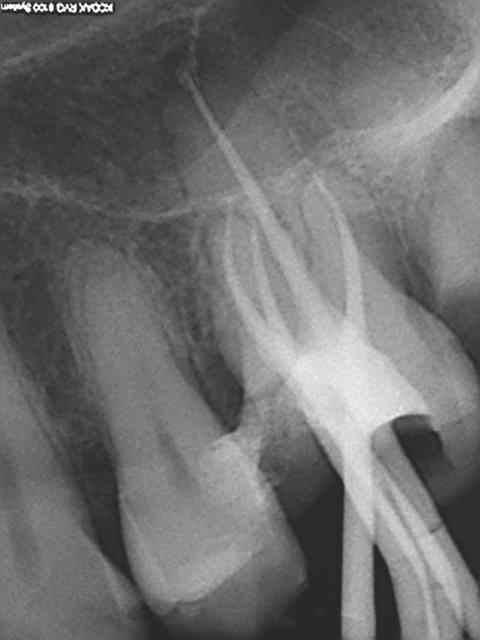

Encore un petit malin bien planqué.

Pas cette fois ci, il y a une autre molaire à pulpecter en file d'attente, en 3/4 d'heure c'était un peu juste. On va faire un co-voiturage pour les ic coiffes après que cette dernière soit passée au R25.-))